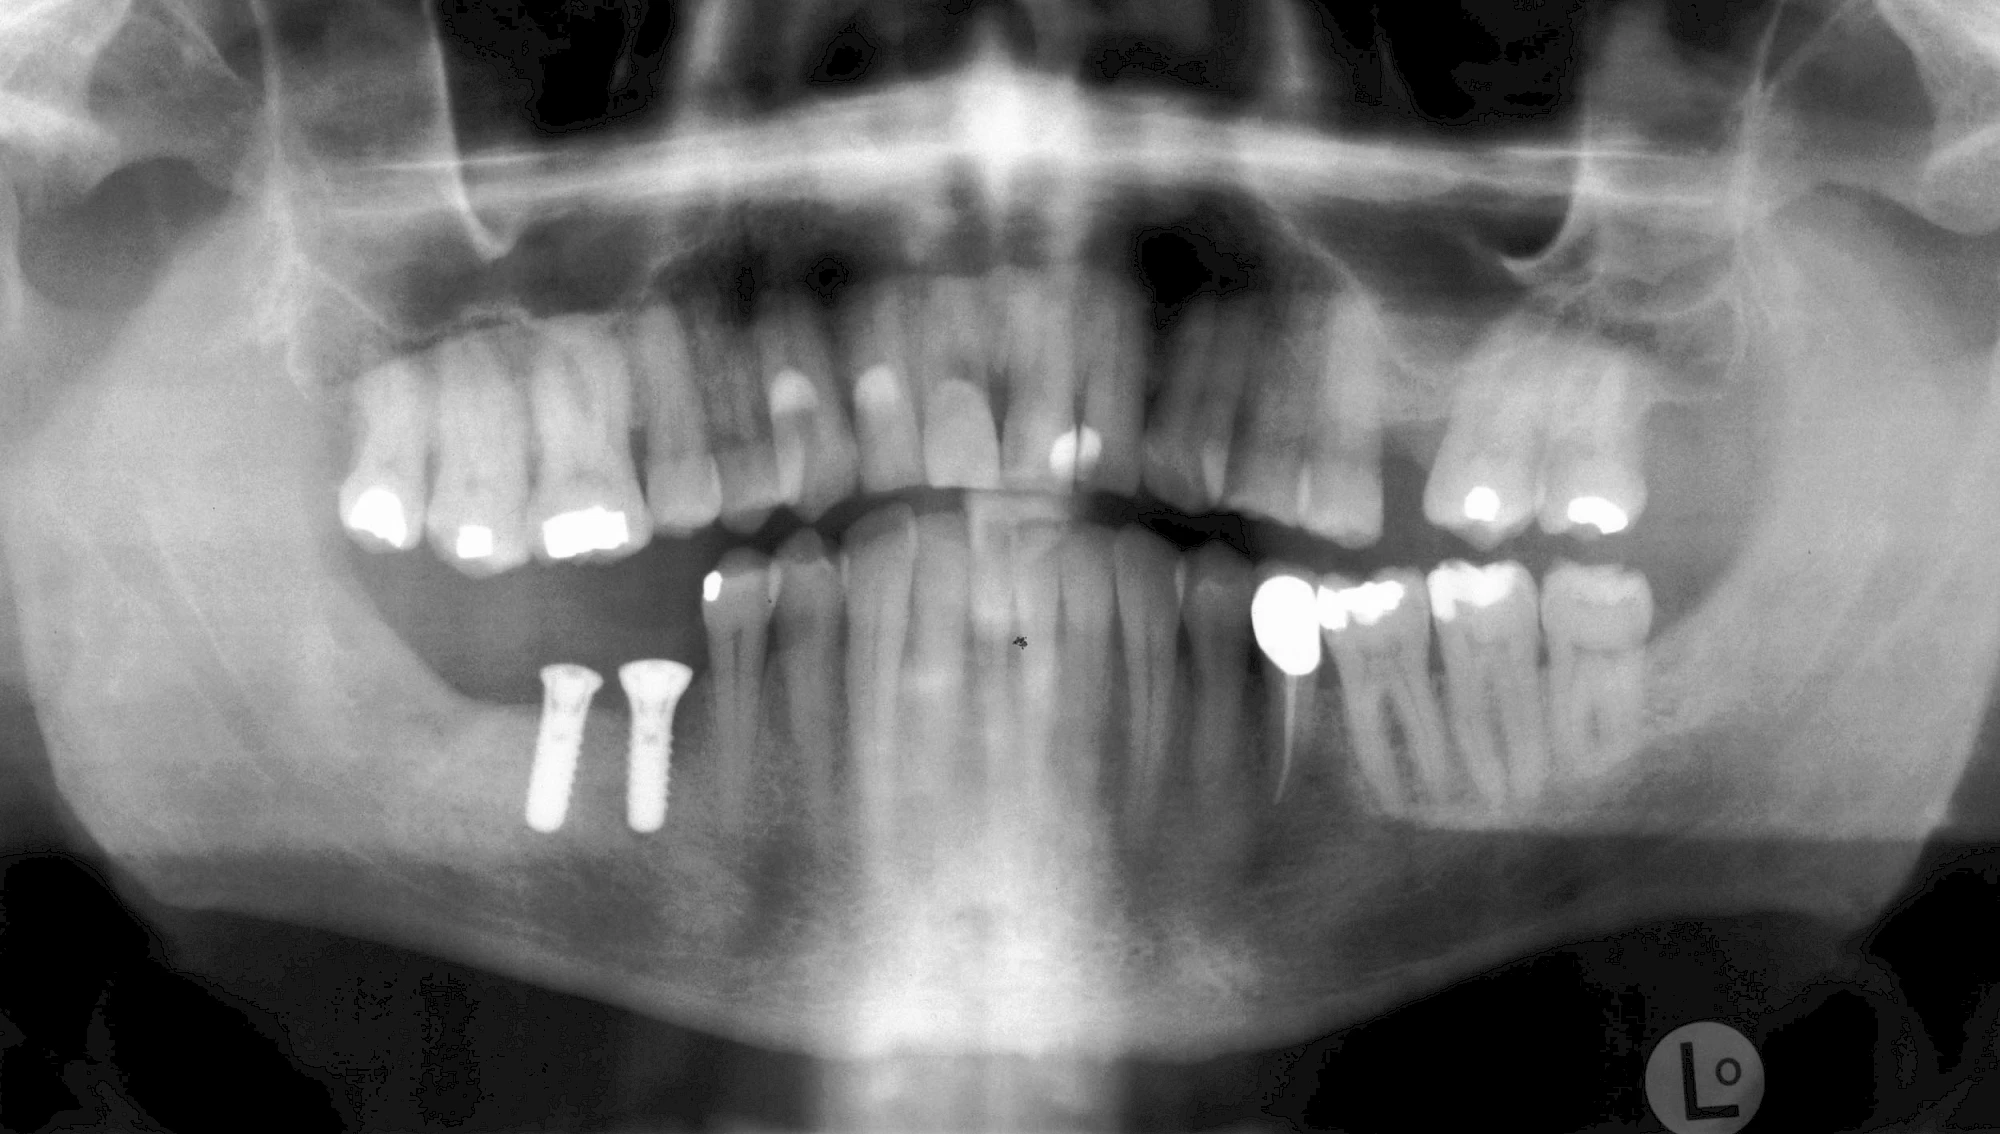

Implantatplanung

Damit Implantate an der richtigen Stelle im Kieferknochen platziert werden könen, gibt es heute vielfältige Möglichkeiten der Planung. In vielen Situationen kann die Erfahrung des Zahnarztes ausreichend sein.

Nicht selten ist jedoch auch eine technisch aufwändigere Vermessung im Vorfeld sinnvoll, z. B.:

- Wenn sich der Kieferknochen abgebaut hat

- Wenn der Nervverlauf im Unterkiefer beachtet werden muss

- Wenn die Ausdehung der Kieferhöhle im Oberkiefer beachtet werden muss

- Wenn wenige Restzähne keine gute Orientierung erlauben

In diesen Fällen kann die Planung mittels verschieden aufwendiger Röntgen-Techniken (Übersichtsaufnahme, DVT) ggf. unter Zuhilfenahme speziell angefertigter Planungsschablonen sinnvoll sein.